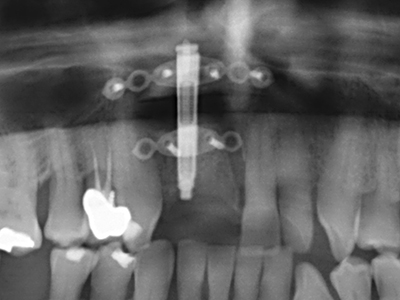

Когато се извършват хирургични процедури върху кост в непосредствена близост до чувствителни структури като кръвоносни съдове или нерви, ротиращите инструменти създават значителен риск за ятрогенно нараняване. Пиезоелектрическите апарати могат да бъдат от помощ при препарация на костно покритие и отстраняване на твърда кост близо до нерви, особено за оголване на нервите след ятрогенно нараняване, както и по време на латерализация на нервите за резекционни и реконструктивни процедури или поставяне на имплант (Фиг. 17-20). Лекият контакт между пиезонакрайника и нерва по принцип не води до нараняване, но ако действате непредпазливо с трионообразни движения или приставки за остатъчен костен субстрат, може да причините временно или перманентно увреждане на нерва. Въпреки това, рискът от увреждане се счита за много по-малък, отколкото при употреба на триони или ротиращи инструменти (Pereira, Gealh et al. 2014).